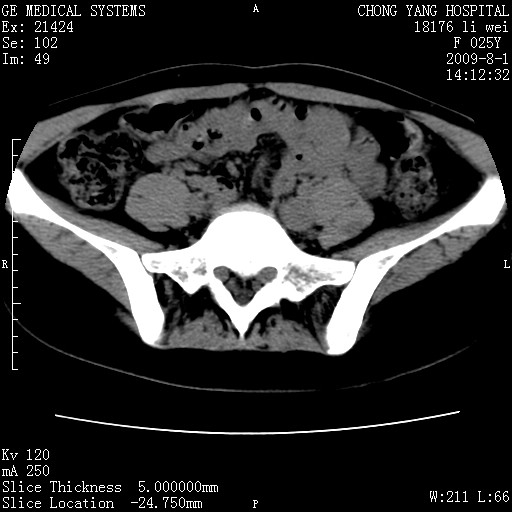

以下是引用pujunzhi在2009-8-1 20:23:00的发言:[br]胸椎旁及背部肌间良性病变,范围广,边界清,沿肌间生长,考虑淋巴管瘤、血管瘤,建议增强扫描。

以下是引用拾荒者在2009-12-30 21:45:00的发言:[br]ct21383:神经纤维瘤病( nf) [br] [br] 神经纤维瘤病。四肢都有,影响美观,四肢上的手术了。[br] [br] [br]谢谢!